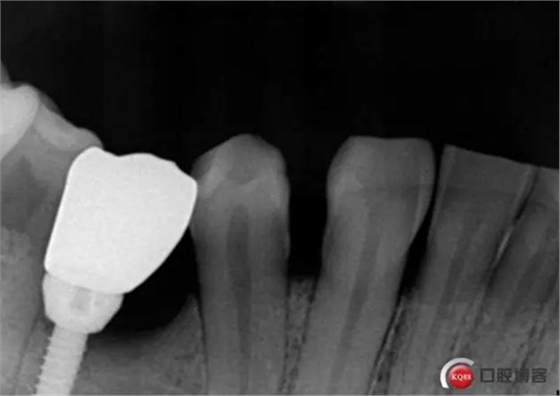

術前

1.jpg

偏遠中植入。 術后病人恢復良好, 無感覺異常。